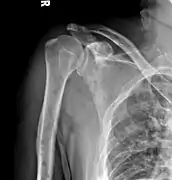

Medical imaging

The diagnostic examination of a person with suspected multiple myeloma typically includes a skeletal survey. This is a series of X-rays of the skull, axial skeleton, and proximal long bones. Myeloma activity sometimes appears as "lytic lesions" (with local disappearance of normal bone due to resorption) or as "punched-out lesions" on the skull X-ray ("raindrop skull"). Lesions may also be sclerotic, which is seen as radiodense.[70] Overall, the radiodensity of myeloma is between −30 and 120 Hounsfield units (HU).[71] Magnetic resonance imaging is more sensitive than simple X-rays in the detection of lytic lesions, and may supersede a skeletal survey, especially when vertebral disease is suspected. Occasionally, a CT scan is performed to measure the size of soft-tissue plasmacytomas. Nuclear Medicine Bone scans are typically not of any additional value in the workup of people with myeloma (no new bone formation; lytic lesions not well visualized on nuclear bone scan).